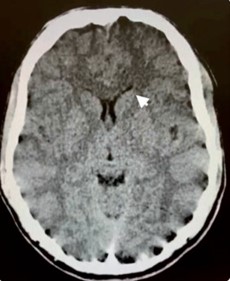

En primer lugar, se puede tratar el caso de los adictos al cannabis, cuya droga tiene efectos sobre el sistema endocannabinoide y en las áreas cerebrales vinculadas con la regulación de las emociones y el estrés. Un estudio de casos y control demostró mediante tomografía por emisión de positrones (PET) cómo la exposición crónica al cannabis, específicamente al THC, reduce la respuesta cerebral a la dopamina, y por ende, mayor puntuación de emocionalidad negativa en los adictos a esta sustancia respecto de los que no lo son. Esto se demostró con el uso de fármacos estimulantes, como el metilfenidato. Este mismo fenómeno también se ha observado con drogas como el alcohol, la cocaína y la nicotina. El cannabis también ocasiona una disminución en el metabolismo de la glucosa cerebral en el cuerpo estriado, tálamo y mesencéfalo(15) (ver Imagen 3).

En relación con este tipo de drogas, se puede citar el reporte de un caso de intoxicación de un varón de 16 años por consumo de píldoras de oxicodona. La TC permitió visualizar la hipodensidad en núcleos caudados, así como una rabdomiólisis de etiología inflamatoria o infecciosa (ver Imagen 14). El paciente presentó otros signos como escasa coordinación, pérdida de conocimiento y dificultad para respirar, que se resolvió en pocos días con intubación y asistencia ventilatoria.(23)

En el caso que se viene ilustrando, la RM mostró T2 difuso con hiperintensidades en el cuerpo calloso bilateral frontal y parietal, así como lesión difusa de la sustancia blanca del cerebelo. Se localizaron áreas de difusión restringida en los ganglios basales bilaterales, lo cual tenía relación con la pérdida neuronal mediada por estrés oxidativo (ver Imágenes 15 y 16). El tratamiento permitió la recuperación progresiva del habla y la orientación de la persona. (23)